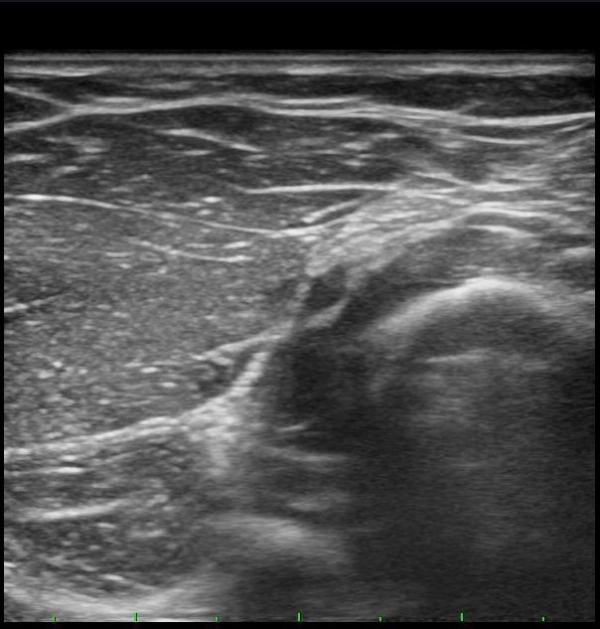

¾Æ·§ÆÈÀ» ȸ³» À§Ä¡¿¡¼­ Èİñ°£½Å°æ Á¾´Ü¸é°Ë»ç¸¦ ½ÃÇàÇÏ´Ï Èİñ°£½Å°æÀÌ µÎ ȸ¿Ü±Ù »çÀÌ¿¡¼­ ¾Ð¹Ú¹Þ°í ȸ¿Ü±Ù ±ÙÀ§ºÎ¿¡¼­ Àú¿¡ÄÚ ºÎÁ¾ÀÌ °üÂûµÊ(±×¸² 4, 5).